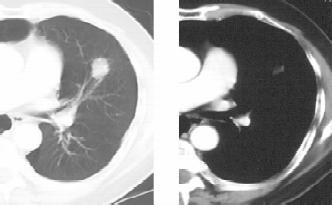

浸润型肺结核多见于成年人,起病缓慢,临床症状视其病灶范围及人体反应性而定。早期及病灶较小者往往无明显症状及体征,常由健康查体时的胸部X线检查发现,显示为锁骨上下片状、絮状阴影,边缘模糊。当人体处于过敏状态且有大量结核菌进入肺部时,病灶呈干酪样坏死、液化,进而形成空洞及病灶的支气管播散(图1-2)。浸润型肺结核伴大片干酪样坏死灶时,常呈急性进展,出现严重毒性症状,临床上称为干酪性(或结核性)肺炎。干酪样坏死灶部分消散后,周围形成纤维包膜;或空洞的引流支气管阻塞,致使空洞内干酪物难以排出,凝成球形病灶,称为“结核球”(图1-3)。当病变处于炎症渗出、细胞浸润甚至干酪样坏死阶段,经恰当的抗结核化学治疗后,炎症吸收消散;遗留的细小干酪样病灶经纤维包围,逐渐失水、干燥甚至钙化,成为残留的结节状病灶,称纤维硬结病灶或临床痊愈。

图1-3 男性,20岁,体检胸片类圆形,左肺结核球